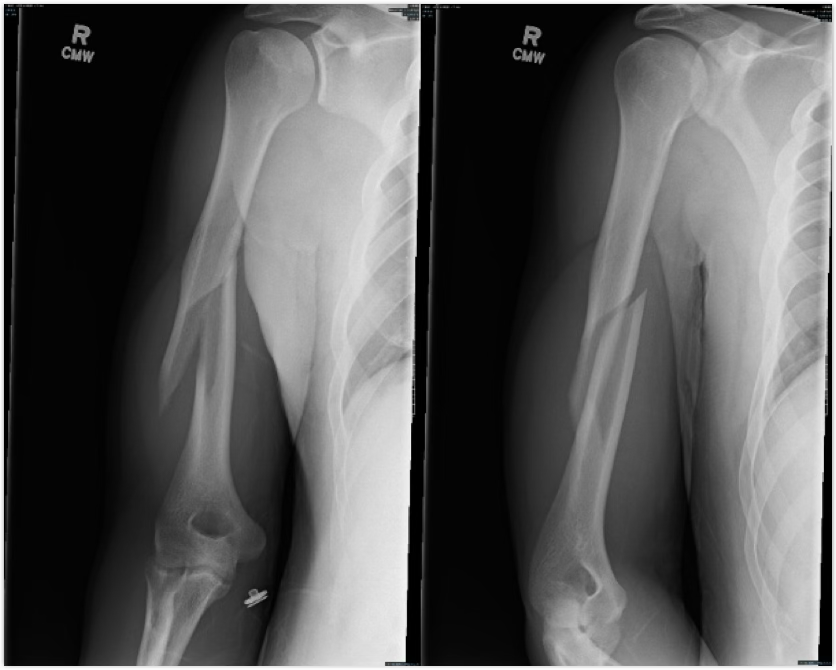

how do humeral fractures occur?

tends to occur with a direct blow or foosh, and can fracture with an eccentric load

watch for growth plate fractures as well

symptoms of a humeral fracture

deformity, pain, swelling, decreased ROM

treatement of a humeral fracture

splint and ship off for a cast or surgery

tends to be 4-8 wk heal time